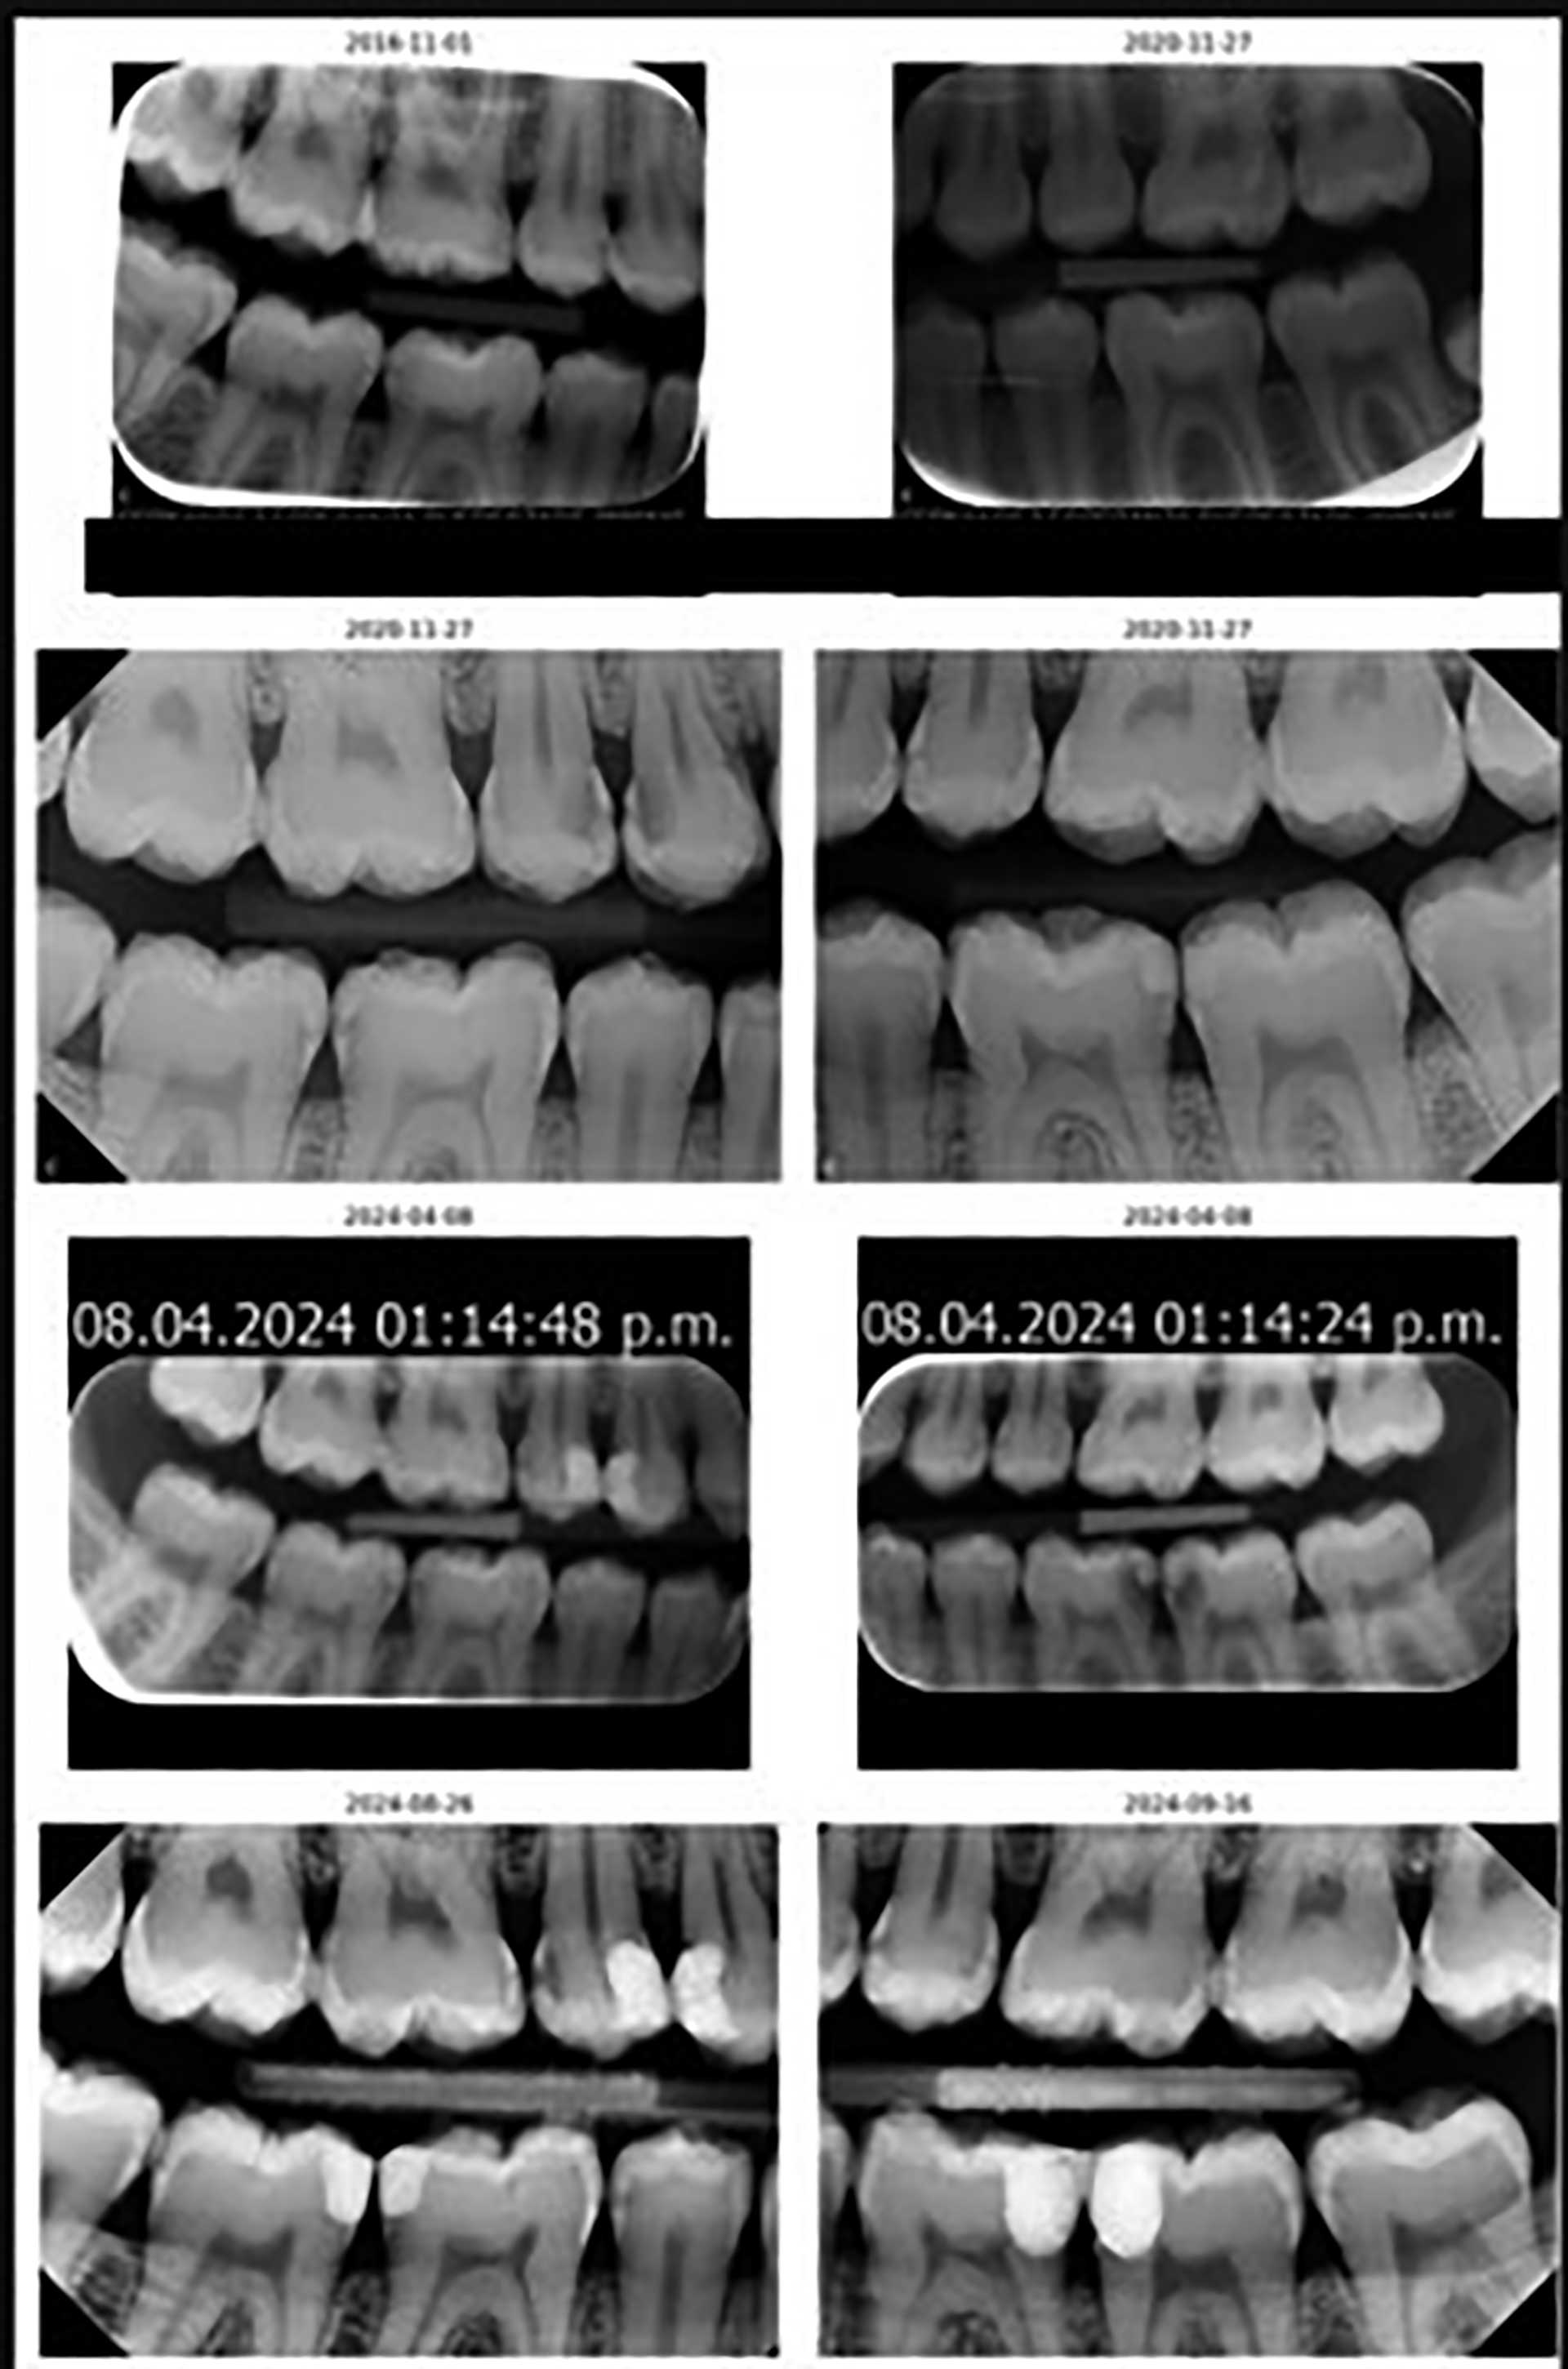

Den kliniske og røntgenologiske (BWs) undersøkelsen fra april 2024 viser at pasientens D1-5MFT er høy: 12 av 28 hvis man ikke tar med visdomstenner (18-48). Antall kariøse tenner er 12 (hvorav 2 tenner har sekundær karies og resten har primær karies), noe som tyder på høy kariesaktivitet Den siste undersøkelsen viser aktivkaries, imidlertid er pasientens karieserfaring lav (pasienten har to komposittfyllinger fra tidligere, tann 36d og 37m) (tabell 3). Det foreligger BWs innhentet fra Den offentlige tannhelsetjenesten helt tilbake fra 2005, 2008, 2009, 2012 og 2016. Disse bekrefter også pasientens lave karieserfaring, og viser at karies har oppstått de senere årene (se figur 2). Videre er gingivale forhold ikke tilfredsstillende da det sees mye plakk interproksimalt og langs gingiva, lett blødende gingiva, men ingen patologiske lommer.

Figur 2. Kronologisk røntgen fra 2016 til 2024. Tannlege B innhenter tidligere røntgenbilder fra den offentlige tannhelsetjenesten og en annen tannlege pasienten var hos i 2020.

Ut fra anamnesen opplyser pasienten at hen ikke har gått jevnlig til tannlegen i alle år, men ut fra det kliniske bilde og røntgenologiske funn kan vi fastslå at pasienten tidligere har hatt lav karieserfaring og lite operativ behandling. Vi ser også at pasientens kariesaktivitet har vært stabil, men de siste årene her det skjedd en forverring.